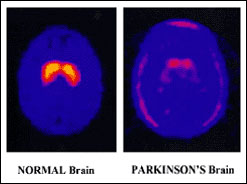

Barbara Myers is back with a new series of Check Up, the health phone-in, where you put your questions direct to the experts. In the first programme, Barbara and her guest will be answering your queries on Parkinson’s Disease. Parkinson’s is a progressive neurological condition affecting movements such as walking, talking and writing. It is named after Dr James Parkinson (1755-1824), the London doctor who first identified Parkinson’s as a specific condition.

In the UK, one in 500 people, or around 120,000 individuals have Parkinson’s. Usually symptoms appear after the age of 50 and the risk of getting Parkinson’s increases with age. Parkinson’s has three main symptoms - tremor, muscular stiffness that can affect posture and forming facial expressions, and a slowing of movement.